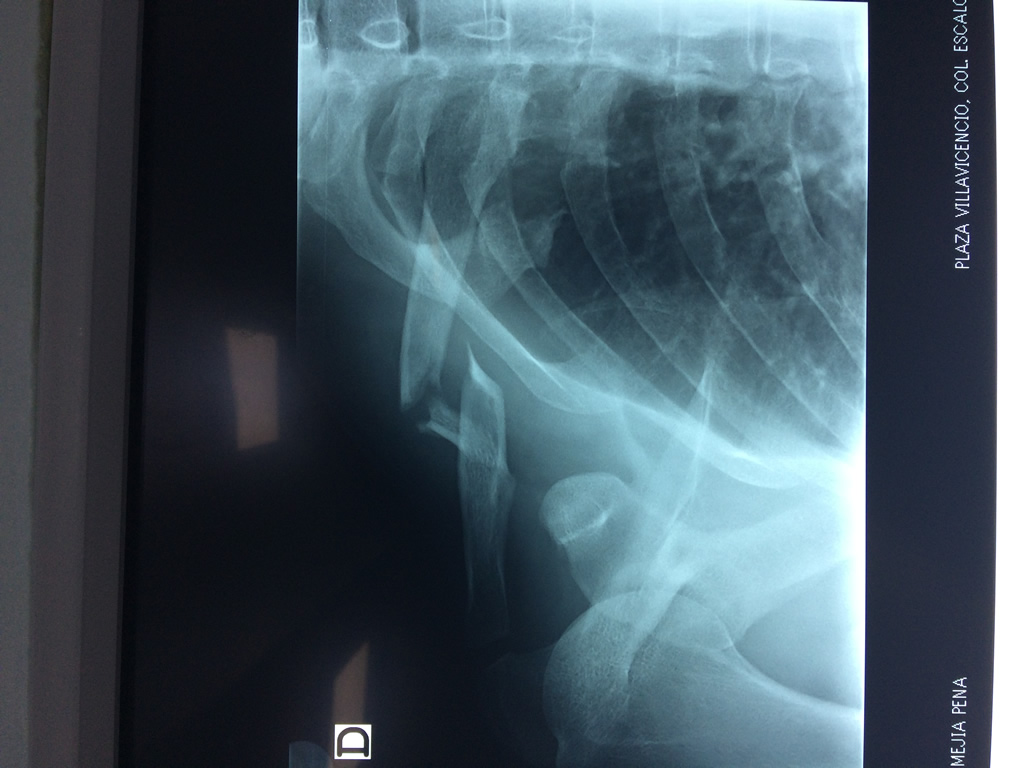

Clavícula

La clavícula es un hueso largo, con forma de "S" itálica, situado en la parte anterosuperior del tórax. Junto con la escápula forman la cintura escapular. Se puede palpar por toda su longitud y se extiende del esternón al acromion de la escápula, siguiendo una dirección oblicua lateral y posterior.